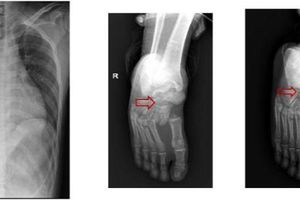

Chấn thương cột sống thắt lưng là một chấn thương nặng có thể gây tàn phế hoặc tử vong.

Chiều 20-5, Bệnh viện (BV) Nhân dân 115 TP.HCM cho biết nơi đây vừa ghi nhận 2 trường hợp chấn thương cột sống thắt lưng do rơi thang máy tầng cao.

Trường hợp 1 là anh NVH (29 tuổi), thợ sửa thang máy. Trong lúc anh H. đang sửa cáp thang máy th́ 1 đồng nghiệp bước vào làm thang quá tải rơi xuống từ độ cao lầu 7.

Anh H. được đưa tới BV trong t́nh trạng tỉnh, tiếp xúc được, tim đều, phổi trong, bụng mềm. Tuy nhiên, anh bị liệt hoàn toàn 2 chân và bí tiểu.Trường hợp 2 là anh TMK (27 tuổi), cũng là thợ sửa thang máy và làm chung với anh H. Trong lúc anh H. đang sửa cáp thang máy th́ anh K. bước vào làm thang quá tải và rơi xuống từ độ cao lầu 7.Anh K. được đưa vào BV trong t́nh trạng tỉnh, tiếp xúc được, tim đều, phổi trong, bụng mềm. Tuy nhiên, anh K. bí tiểu và đau cột sống thắt lưng, liệt hoàn toàn 2 chân.

Anh H. và anh K. được các BS chẩn đoán chấn thương cột sống thắt lưng và tiến hành phẫu thuật cấp cứu làm cứng cột sống, nắn chỉnh cột sống ngực - thắt lưng, cố định các cột sống… Nhưng cả anh H. và anh K. rất khó trở về cuộc sống b́nh thường bởi mất khả năng đi lại.

BS Chu Tấn Sĩ, Trưởng khoa Ngoại thần kinh BV Nhân dân 115, cho biết chấn thương cột sống thường gặp trong sinh hoạt, tai nạn lao động. Trong đó, tai nạn lao động chiếm 20% và thường do té từ trên cao.